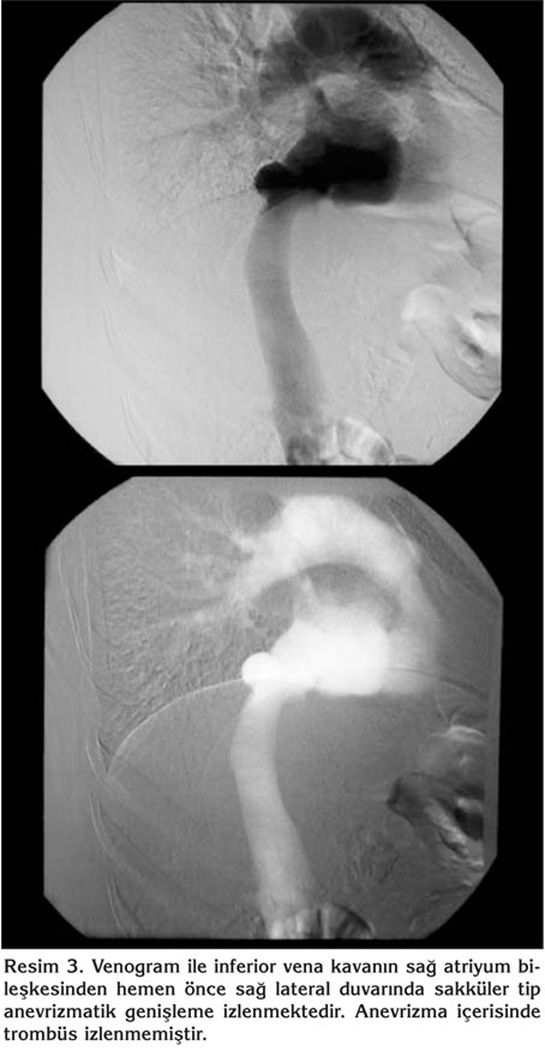

Elli sekiz ya??nda kad?n hasta, tekrarlayan ?ks?r?k ?ikayetiyle hastanemize ba?vurdu. Hasta ev han?m? idi ve sigara kullanm?yordu. ?yk?s?nde uzun s?redir nonprod?ktif ?ks?r?k ?ikayetine ek olarak s?k bo?az temizleme hissi ve bo?az a?r?s? mevcuttu. ?la? kullan?m ?yk?s? yoktu. Fizik muayenesi ve solunum fonksiyon testleri normal s?n?rlarda idi. Radyolojik tetkiklerinde; PA akci?er grafisi normal s?n?rlarda olan hastan?n waters grafisinde sa? maksiller sin?zit ile uyumlu bulgular? ve kontrastl? toraks bilgisayarl? tomografisi (BT)'nde diyafragma ?zerinde, sa? atriyum posterior kom?ulu?unda, ?VK'da anevrizmal geni?leme saptand? (Resim 1, 2). Yap?lan venografi incelemesiyle torasik ?VK segmentinde sakk?ler anevrizmal dilatasyon varl??? teyit edildi (Resim 3).

?VK anevrizmalar? ?o?unlukla asemptomatik olup, hastalarda kar?n a?r?s?, gastrointestinal sistem kanamas?, akut ven?z okl?zyon, pulmoner emboli ve ?l?m g?r?lebilir (2,3). Bizim hastam?zda asemptomatik ?VK anevrizmas? tesad?fen saptanm??t?r. ?VK anevrizmas?n?n tan?s?ndan genellikle ba?ka nedenler i?in yap?lan ara?t?rmalar s?ras?nda saptanan fizik muayene ve radyolojik g?r?nt?leme y?ntemleri bulgular?yla ??phelenilir. Akci?er grafisi, BT, Dupleks renkli doppler ultrasonografi, manyetik rezonans anjiyografi ve konvansiyonel venografi gibi g?r?nt?leme y?ntemleri tan?n?n do?rulanmas?nda kullan?labilir (5). BT ile ?VK'n?n normal boyutu infrahepatik segment i?in 2.7 ? 1.5-3.7 cm iken, kardiyak segment i?in 2.39 ? 0.5 cm'dir (1,9). Bizim olgumuzda da BT ile saptanan suprahepatik anevrizman?n boyutu, 3.3 x 4 x 3 cm idi ve tan? venografiyle do?ruland?.